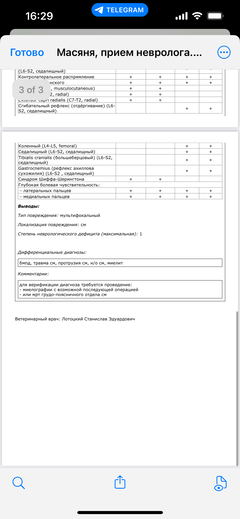

Ярко выраженная болезненность в области крестца, на обезболе полегче. По результатам приема невролога проведена миелография - множественная компрессия, возможно опухоль, возможно грыжа, нужно удалять...